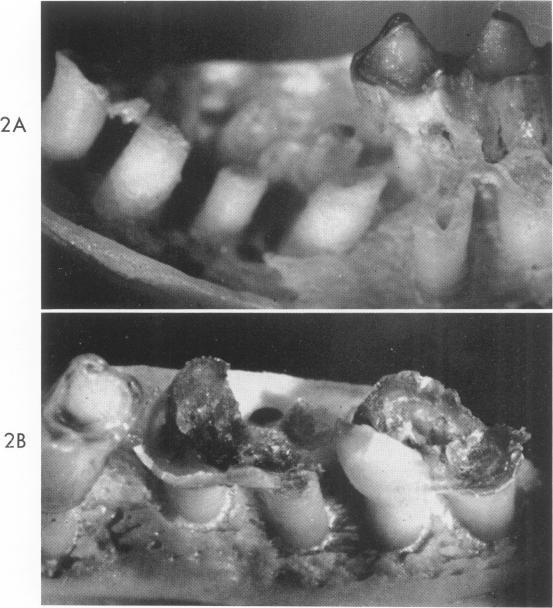

Ecologic factors in dental caries. The fate of antibiotic-resistant cariogenic streptococci in hamsters.

Am J Pathol. 1963 Jun;42(6):759-72.